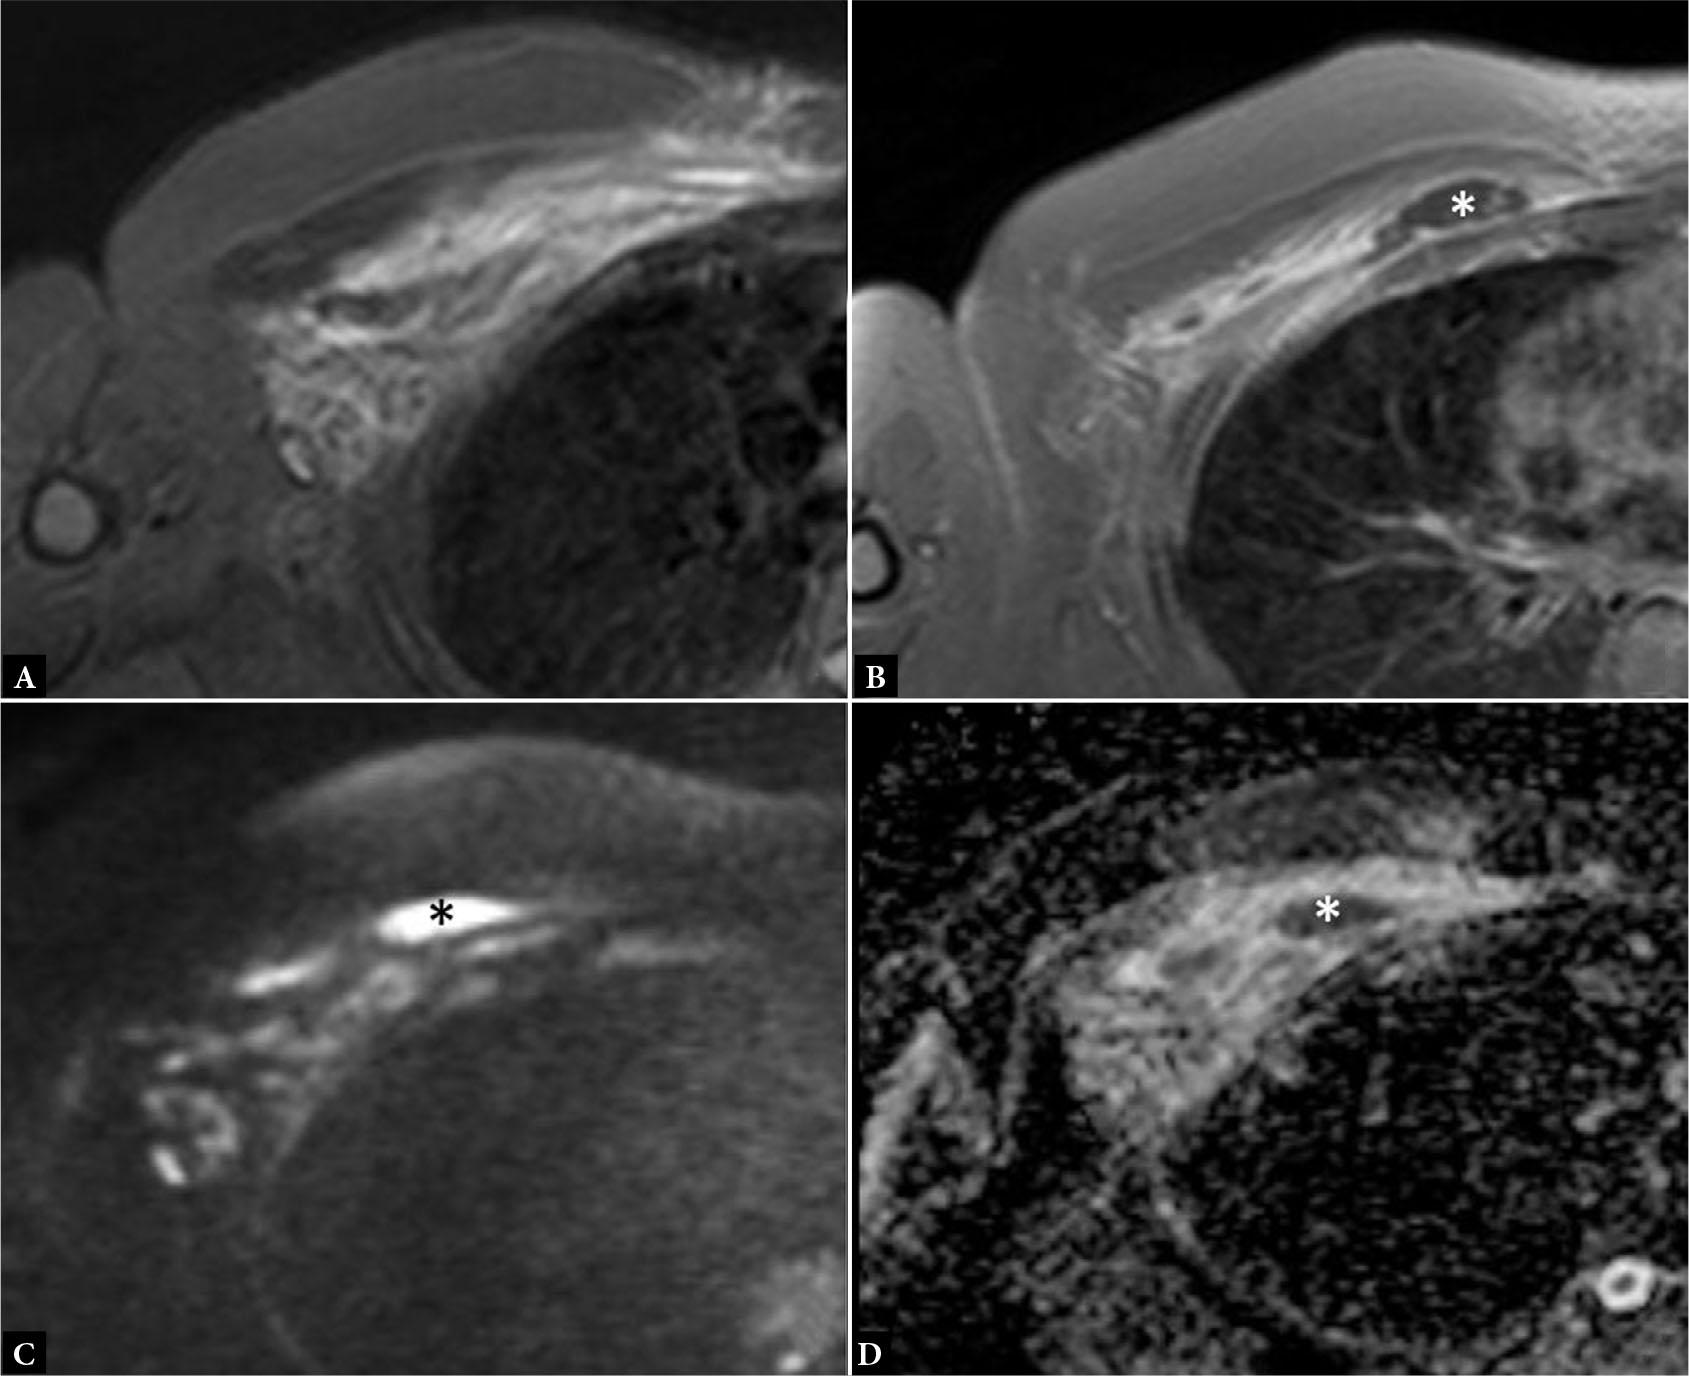

Fig. 15.

A. Axial fluid-sensitive MR image shows hyperintensity in the PM muscle. B–D. Post contrast axial T1 MR image with fat saturation (B) shows a region of peripheral enhancement (asterisk) in the medial fibers of the PM with corresponding high diffusion weighted imaging (C) and low apparent diffusion coefficient (D) values, in keeping with intramuscular abscess. Note the similarity in appearance of Figures 15A and 14B, underscoring the importance of clinical history